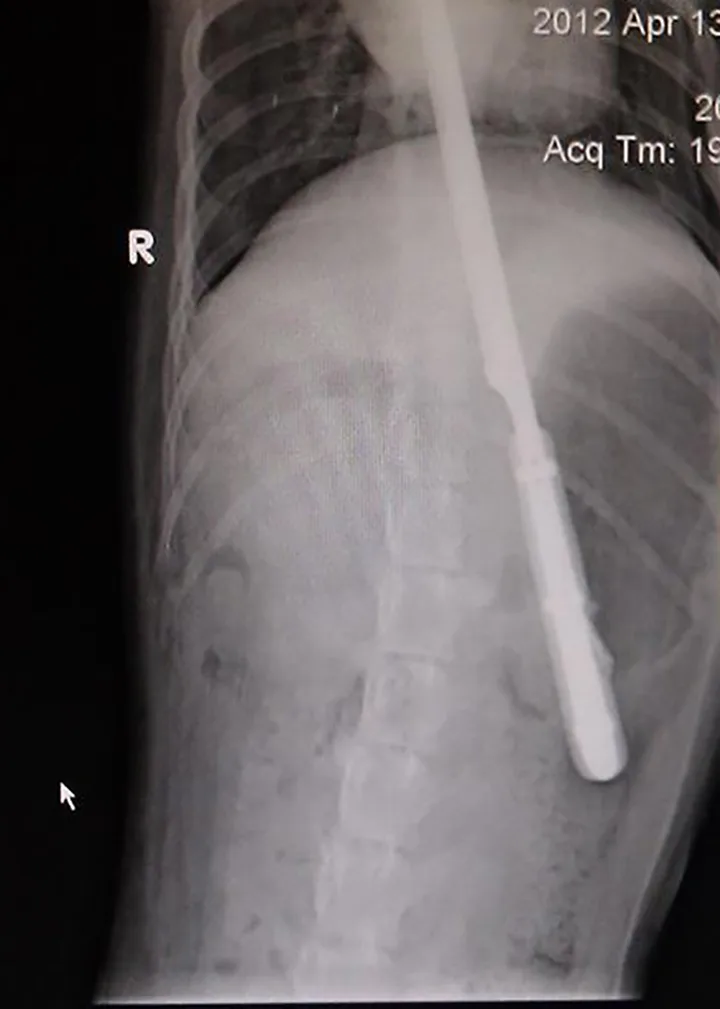

We asked our Facebook audience, "what is the coolest clinical photo you have on your phone right now?" The response was overwhelming. We sorted through more than 600 responses to find our favorite radiographs. Here are those images and their stories. Thank you to everyone who shared their photos.

"This energetic 10-month-old Labrador swallowed a 12-inch serrated knife. The puppy was bouncing off the walls when he was brought in and it was hard to keep him still. Surgery went well and amazingly, nothing was damaged!"—Katelyn E